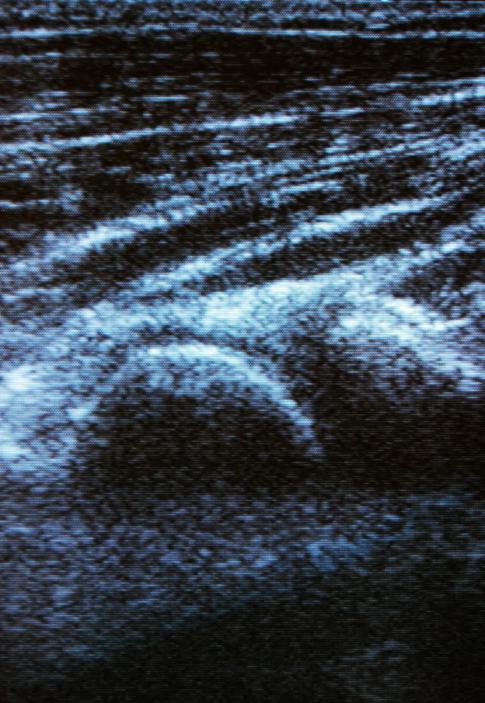

Abdomensonografie

Mit der Abdomen (Bauch) Ultraschall Untersuchung

lassen sich gezielt bestimmte Strukturen im Bauchraum

darstellen. Aus den gewonnen Bildern lassen sich

Rückschlüsse auf eine Vielzahl von Erkrankungen

ziehen. z.B:

- Leber und Gallenwege: Steine, Gelleaufstau,

Tochtergeschülste im Rahmen einer Tumornachsorge

- Nieren: Nierensteine, Größenveränderungen, Harnstau

- Gefäße: Bauchschlagadererweiterungen, Durchblutungs

verhätnisse,

- Bauchspeicheldrüse: chronische Entzündungen